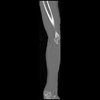

7 CUERPO,CE,Sagittal,3.000,CUERPO,Sagittal,